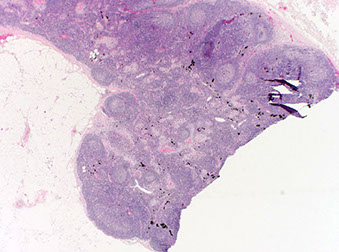

- Duodenal-type FL